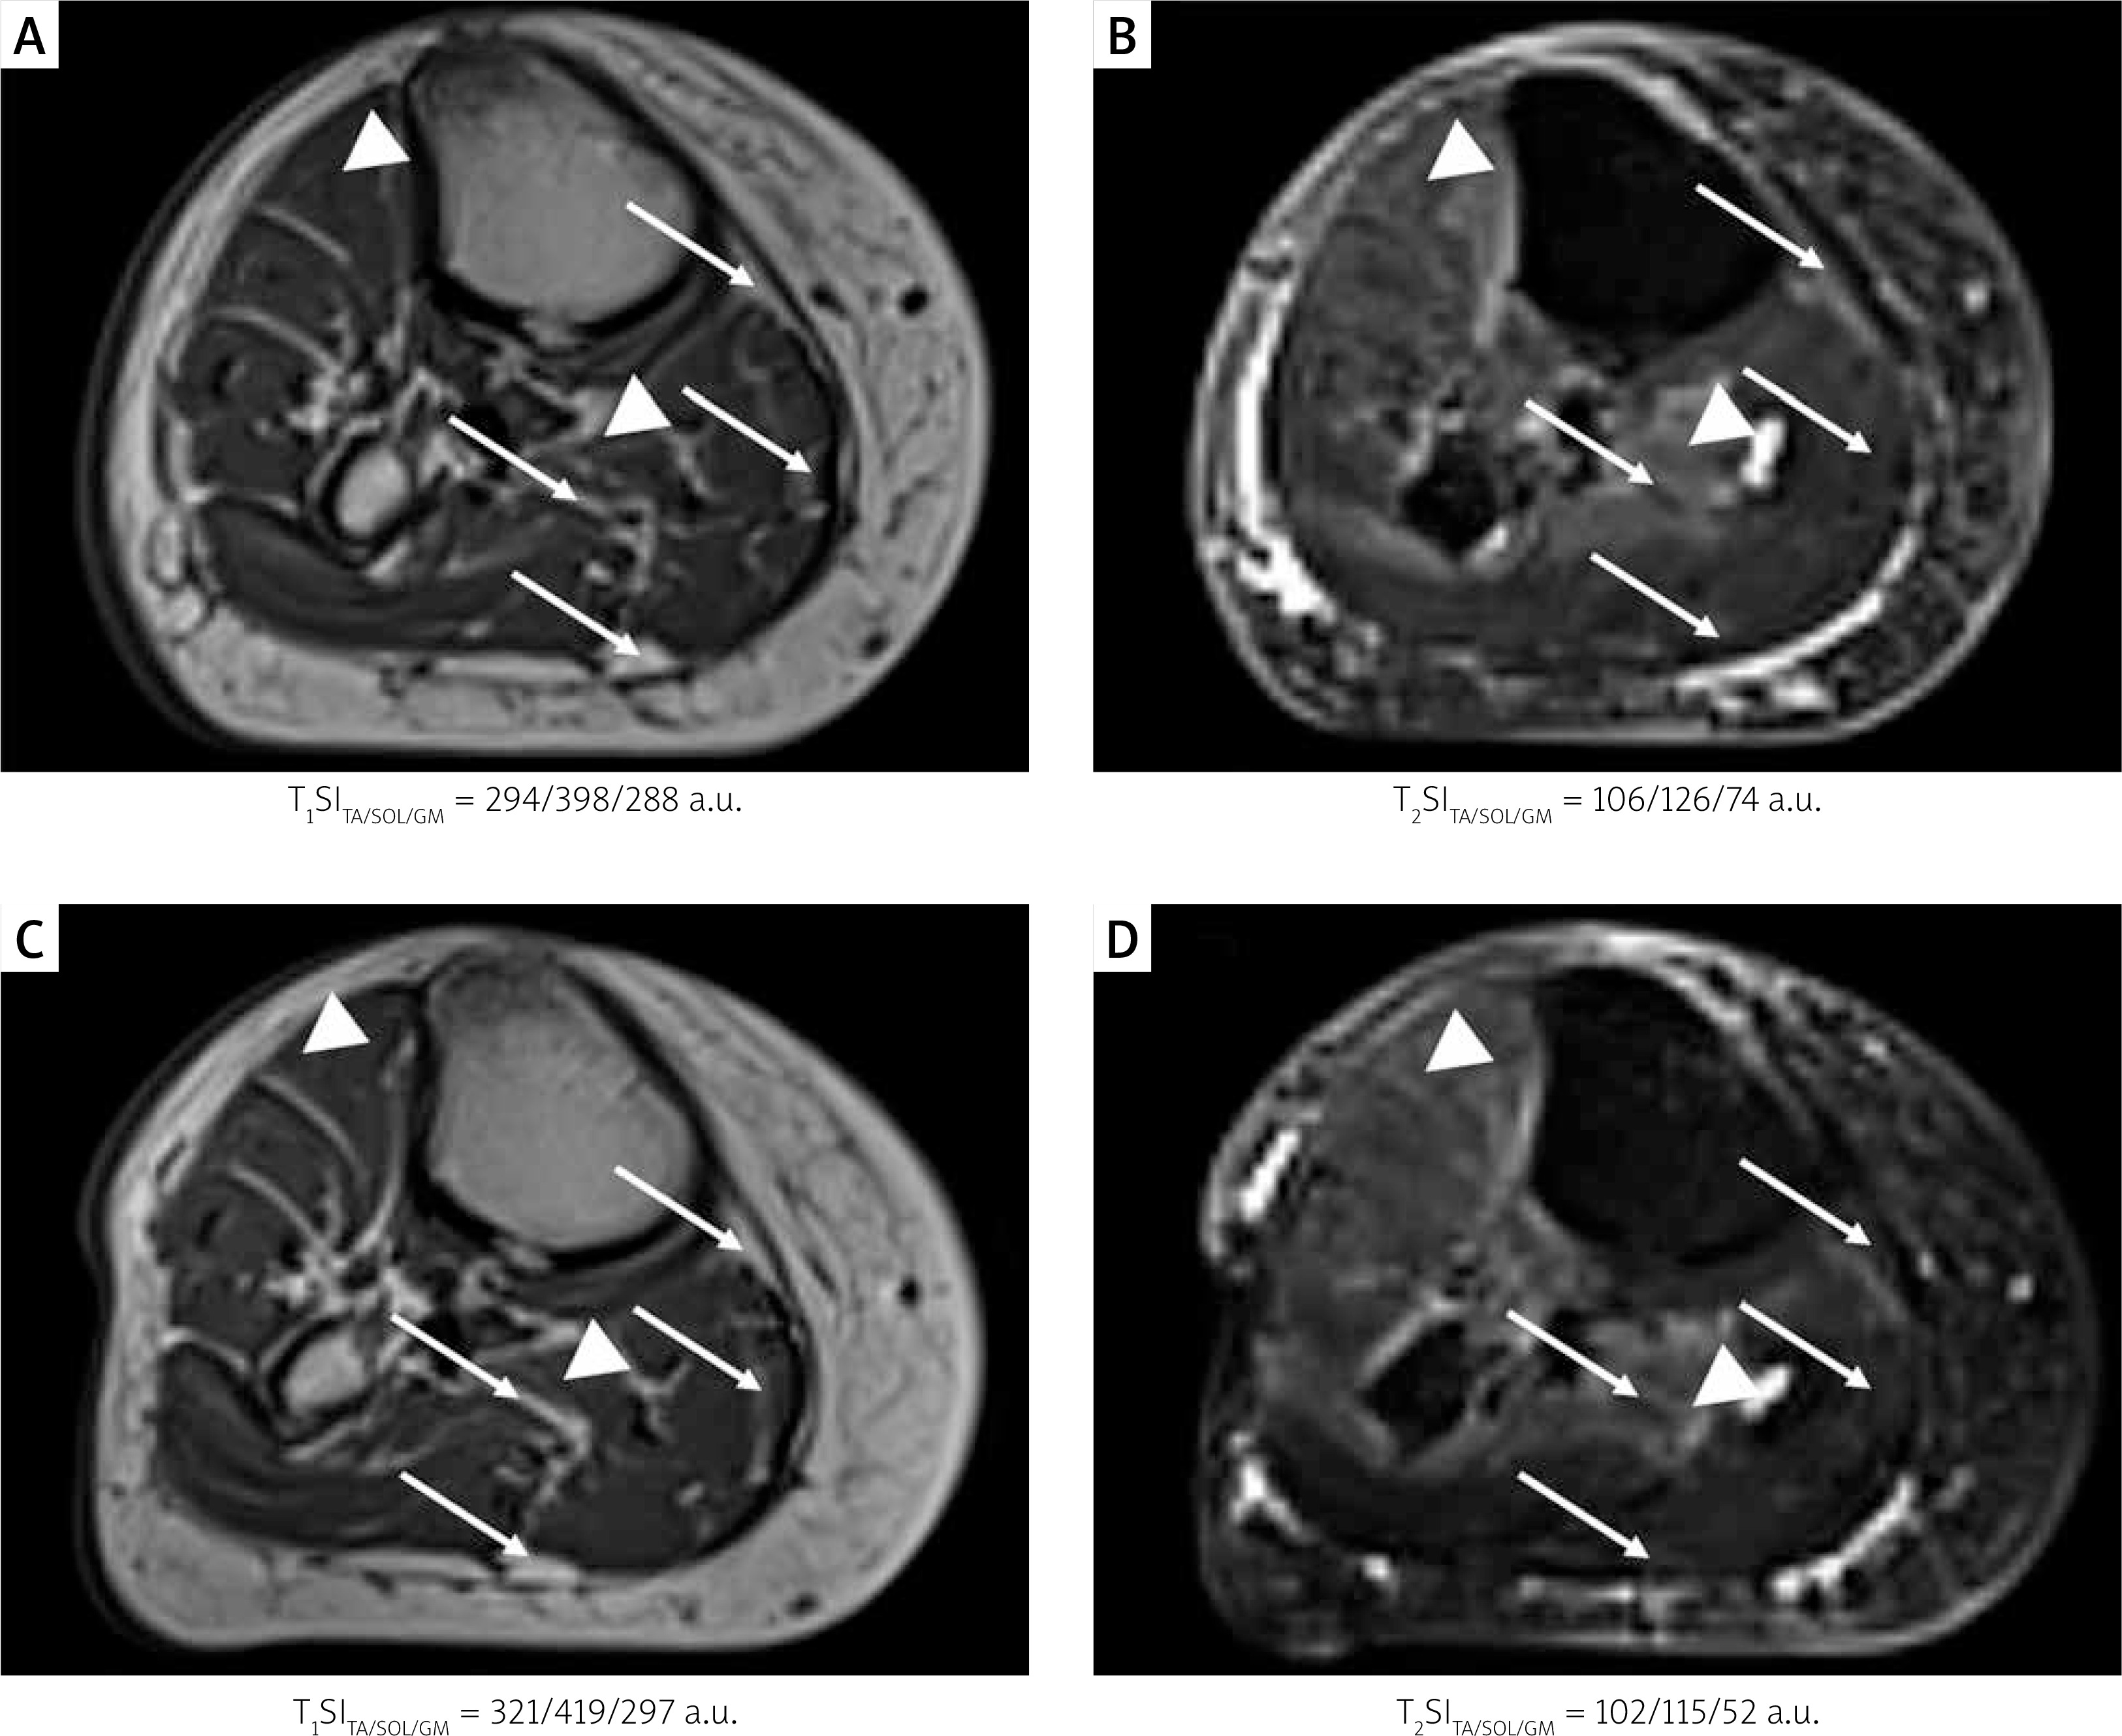

Muscles’ condition was evaluated based on T1- (T1WI) and T2-weigthed images (T2WI; Figure 1), obtained transversely on a 3T MR system (Siemens Skyra 3 T, Erlangen, Germany) using an eight-channel TORSO body coil with the application of turbo spin echo (TSE) and turbo inversion recovery magnitude (TIRM) with fat suppression pulse sequences, respectively. Complementarily, diffusion tensor imaging (DTI) was performed using the Echo Planar Imaging (EPI) sequence with six diffusion gradient directions. In the DTI protocol, b-value = 350 s/mm2, number of scans, NoS = 1, while slice thickness was equal to 8 mm. The BSD-DTI calibration method [1, 2] was applied before the quantitative analysis, for which it was shown recently to have substantial applicability [3]. The following DTI parameters were analyzed: the second and third eigenvalues (λ2 and λ3, respectively), mean (MD), longitudinal (DL) and transversal (DT; mean of λ2 and λ3) diffusivity, and fractional anisotropy (FA), by using the in-house BSD-DTI software (BSD-DTI ver. 2.0, AGH UST, Krakow, Poland). For comparison, mean parameters for 3 healthy volunteers were presented (control, C). A single muscle from each compartment was chosen as representative: tibialis anterior (TA), soleus (SOL) and gastrocnemius medialis (GM).

Figure 1

Axial T1-weighted FSE (T1WI) and T2-weighted TIRM (T2WI) images of calf of a 76-year-old woman with PAD. A, B – T1WI (A) and T2WI (B) before the medical intervention (examination E1); C, D – T1WI (C) and T2WI (D) after the injections of CardioCell based on mesenchymal stem cells (MSCs) or placebo in a double-blind RCT (examination E2). Regions of fatty infiltration (arrows) and edema-like signal (arrowheads) can be recognized. In the picture, analyzed calf muscles are indicated by the following abbreviations: tibialis anterior (TA), soleus (SOL), gastrocnemius medialis (GM), for which T1 and T2 signal intensities (T1SI and T2SI, respectively) are shown below the image

Recently it was shown that the BSD-DTI method is crucial for the quantitative evaluation of the muscle condition and intervention effect in PAD. In this study we found that diffusion can also reflect different disease courses. MRI of the patient from this work revealed chronic muscle denervation that resulted in atrophy with fatty infiltration reflected in a hyperintense signal on T1WI and a corresponding low-intensity signal on T2WI [4], similarly to a previously reported patient [3]. In contrast, anterior and deep posterior compartments showed a high-intensity, edema-like signal on T2WI (Figure 1), while neoangiogenesis in the muscle bulk was hardly recognized, which is opposite to the previously reported patient [3].

After the intervention (E2) all muscles are characterized by higher T1 signal intensity (T1SI) and lower T2 signal intensity (T2SI) (Figures 1 C and D, respectively), which is associated with T1 and T2 decreasing. This means that they approached the values reported for normal muscles (T2 = 27–38 ms [5] and T1 = 1420 ms [6] in comparison to T2 = 133 ms for fat [6]). At the same time, MD and DT decreased, which suggests the reduction of the edema. Moreover, GM and TA showed improved muscle anisotropy and FA, visible also as the improved structure (density and direction of fibers) on the tractographic DTI representation (Figures 2 B and C). A slight decrease of λ2 and λ3 in TA and GM seems to be connected with edema recovery rather than fatty degeneration. In SOL, apart from decreased DT, λ2, λ3 and MD indicatory for detumescence, fiber tract density (Figures 2 B and C, arrowheads), FA and DL decreases can also be observed, which suggests overall muscle dehydration. The intervention caused changes from peripheral to internal compartments, which will be assigned to the MSC therapy or placebo after the unblinding.